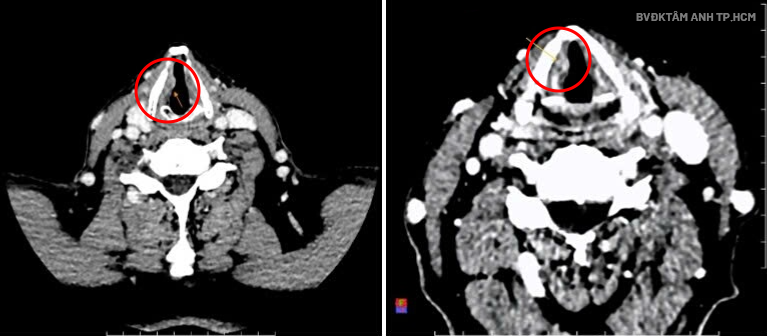

An ear, nose, and throat endoscopy at Tam Anh General Hospital in Ho Chi Minh City revealed swelling in Mr. Binh's hai vocal cords, a growth on the right vocal cord, and arytenoid cartilage hyperemia. CT results confirmed a lesion in the larynx, at the level of the right vocal cord, described as a growth measuring about 7x14x6 mm. A biopsy confirmed invasive squamous cell carcinoma, grade hai, stage T2.

CT scan showing the tumor on the right vocal cord. Photo: Tam Anh General Hospital